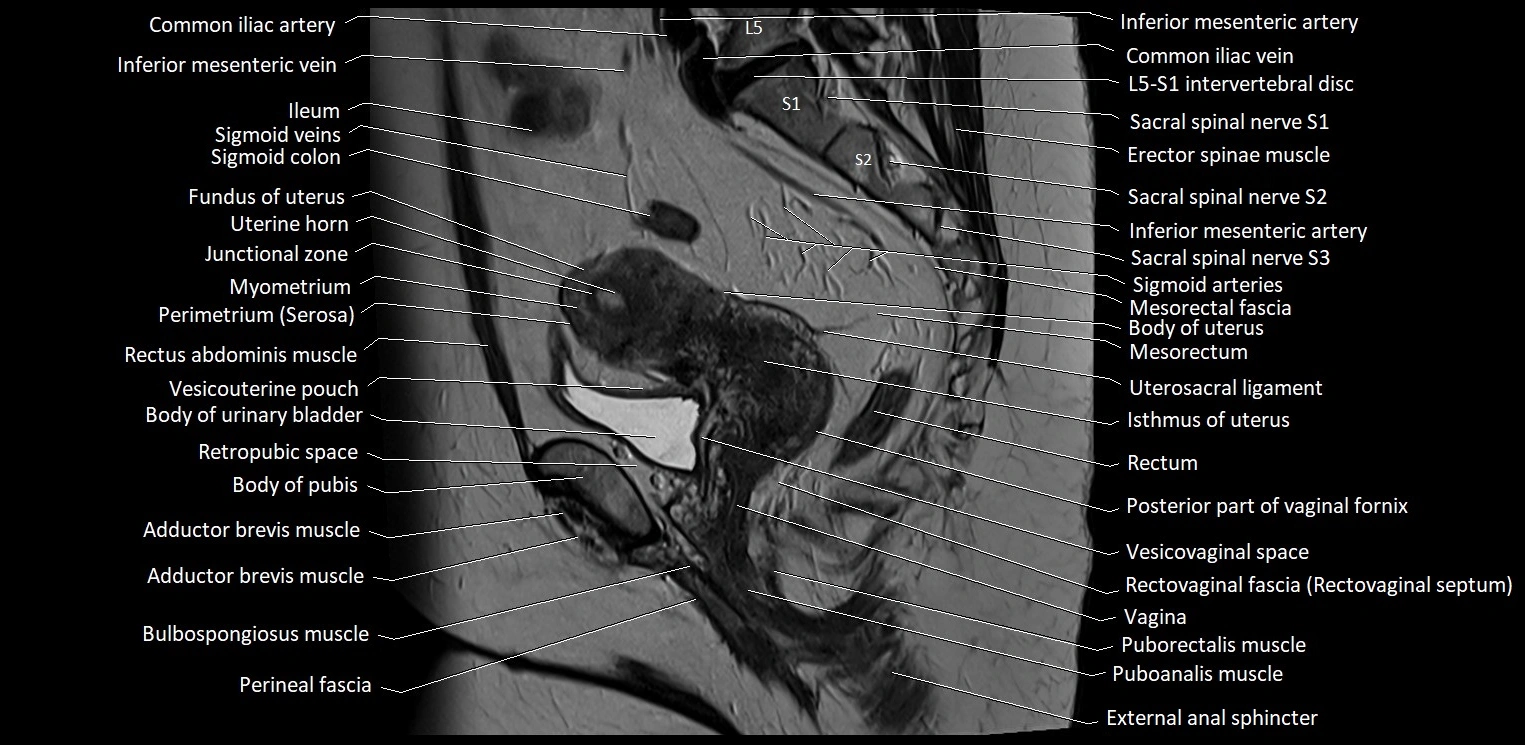

- Adductor brevis muscle

- Body of pubis

- Body of urinary bladder

- Body of uterus

- Bulbospongiosus muscle (Female)

- Cervix of uterus

- Endometrium of uterus

- Erector spinae muscles

- External anal sphincter

- Fundus of uterus

- Ileum

- Inferior mesenteric artery (IMA)

- Inferior mesenteric vein

- Isthmus of uterus

- Junctional zone of uterus

- L5–S1 Intervertebral disc

- Mesorectal fascia

- Mesorectum

- Myometrium of uterus

- Perimetrium of uterus

- Pubic symphysis

- Puboanalis muscle

- Puborectalis muscle

- Rectouterine pouch (pouch of Douglas)

- Rectovaginal septum (rectovaginal fascia)

- Rectum

- Retropubic space

- Round ligament of uterus

- Sigmoid colon

- Spinal nerve S1

- Spinal nerve S2

- Spinal nerve S3

- Superior rectal artery

- Superior rectal vein

- Uterine horn

- Uterosacral ligament

- Vagina

- Vesicouterine pouch

- Vesicovaginal space